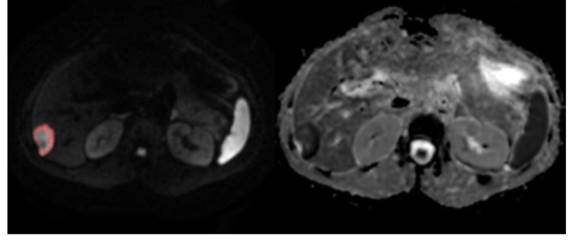

Figure 2

DrEye Lesion segmentation on b1000 and normalized ADC histogram.

J Cancer Image

Following the calculation of ADC values on a pixel by pixel basis, histogram analysis was performed utilizing an in-house developed software tool (DrEye Histogram Plugin, ICS FORTH, Heraklion, Greece). Apart from ADC maps, both b0 and b1000 maps were used to perform histogram analysis. Multiple regions of interest constituting a volume of interest (VOI) were manually drawn on b1000 images on the basis of high signal intensity and then copied to the ADC maps. Areas of necrosis as identified on b0 were excluded from the VOIs. Pixels assigned to the lesion were segmented by a “magic wand” tool on the basis of high signal on b1000 with adjustable user-depended degree of tolerance and then copied to the ADC map by DrEye Histogram Plugin. ADC histograms were generated from all pixels belonging to the VOI, and the following parameters were calculated for each patient: min, max, mean, median, standard deviation, skewness, kurtosis, and 5th, 30th, 70th, and 95th percentiles.